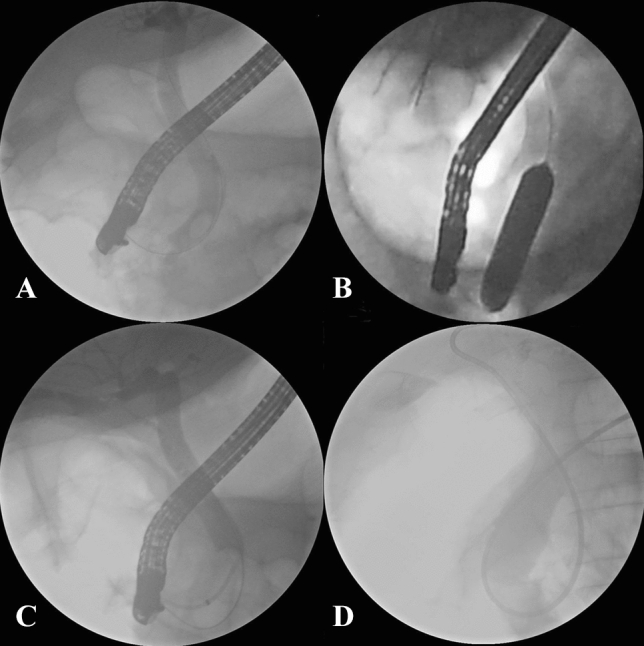

Selective cannulation of the CBD was performed by a sphincterotome with a guidewire. The double-guidewire technique or the transpancreatic precut was applied in some difficult cases, such as inflammation or special morphology of papilla, and periampullary diverticula. For cases with CBD stones embedded within the papilla, needle-knife papillotomy was performed. For type B diverticula, we first exposed the papilla by eversion using biopsy forceps, or fixation by metal clip, or submucosal injection of saline, and the double-guidewire technique was often applied.

After cannulation of the CBD and cholangiography, endoscopic sphincterotomy (EST) alone or small EST combined with endoscopic papillary balloon dilation (EPBD) was performed. For cases with either abnormal coagulation (because of taking antiplatelet and anticoagulation medicine) or with type B diverticula, EPBD alone was performed.

Mechanical lithotripsy was applied when CBD stones were too large. However, if a patient was in poor condition or had large CBD stones with type B diverticula, endoscopic retrograde biliary drainage (ERBD) alone was performed. Three months later, when stones would have become smaller and softer, a subsequent ERCP was performed for removal of CBD stones.

The guidewire was always kept in bile duct during the whole procedure, and in most cases endoscopic nasobiliary drainage (ENBD) was placed after removal of CBD stones, especially in cases with mechanical lithotripsy. For cases with multiple pancreatic-duct cannulations, endoscopic retrograde pancreatic drainage (ERPD) was performed.

PEP is one of the most feared complications of ERCP. It occurs in 5–19.8% of patients after endoscopic papillary balloon dilation (EPBD)23. The balloon dilation of the sphincter of Oddi may cause compression, spasm and edema of the distal pancreatic duct, leading to the restriction of pancreatic juice flow and the occurrence of pancreatitis24. It is reported that, compared to EPBD alone, small EST combined with EPBD can reduce the risk of PEP by guiding the orientation of the dilation towards the CBD, which prevents pressure overburden on the main pancreatic duct25. Moreover, large openings of the bile duct in association with large balloon dilations could eliminate unintended pancreatic-duct cannulizations in ensuing stone extractions. The guide wire was kept in the CBD for direction. This is very important, especially for type B PAD, since predicting the direction of the bile duct is very difficult. Another key point to decrease the incidence of PEP is selective cannulization of the CBD when performing the ERCP26. In our study, we used a sphincterotome with a guide wire instead of a catheter, to avoid injecting contrast medium into the pancreatic duct. Our study showed that there was no significant difference between the two groups concerning PEP and hyperamylasemia, and that all cases of pancreatitis were mild, recovering after conservative treatment in less than 72 h.

Perforation is another fatal complication of therapeutic ERCP. Since PAD consists of thin mucosa lacking smooth muscle28, it may increase the potential risks of perforation during therapeutic ERCP procedures. In this case, the length of EST is relatively short, and outcomes of therapeutic ERCP were influenced19. However, during balloon dilation after small EST, the endoscopists could observe the dilation status of the ampulla by endoscopy and fluoroscopy, and the risk of perforation thereby could be reduced. To minimize the risk of perforation, the pressure of the balloon should be increased gradually, and the size of the dilated balloon should not exceed the size of the CBD. If the CBD stones are too large in patients with type B PAD, ERBD was performed for drainage and to relieve symptoms, and thereafter therapeutic ERCP was performed 3 months later. Consequently, there were no cases of perforation in either group in our study. Moreover, the combination of EPBD with small EST provided a spacious opening of the bile duct, reducing the need for mechanical lithotripsy29.